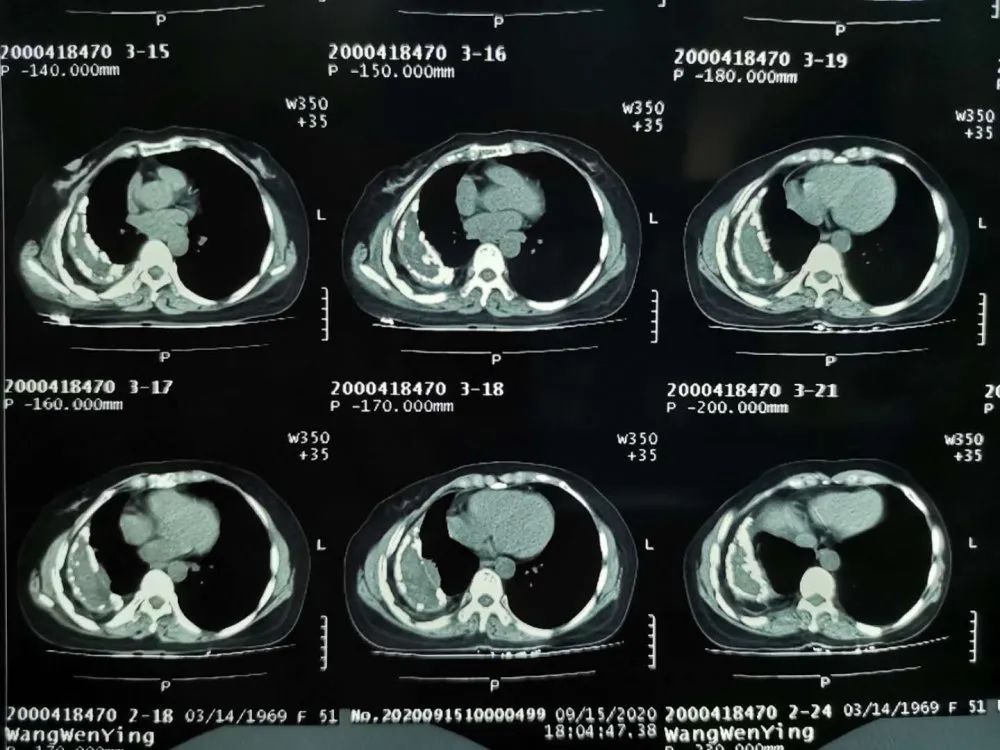

近期,江西省第三人民醫(yī)院胸外科收治多例“結(jié)核性膿胸”年輕病例,大部分都是30歲以內(nèi)的年輕人。23歲的阿黃就是諸多膿胸大軍的其中一員。阿黃于1月前無明顯誘因出現(xiàn)咳嗽咳痰,伴右側(cè)胸痛,于我院就診,隨后收治外三科胡欣春主任組下,完善相關(guān)檢查。患者胸水結(jié)核抗體陽性,胸部CT提示雙側(cè)結(jié)核性胸膜炎,經(jīng)組討論,決定于9月22日全麻下行外科手術(shù)治療,由于病灶范圍極大,纖維板已形成鈣化,所以決定取右前外側(cè)切口,長度約25cm,依次切開皮膚、皮下組織及肋外肌層,切除第7肋,沿第7肋床放入胸腔鏡,發(fā)現(xiàn)全胸膜腔閉鎖,右側(cè)胸腔有一枚較大的膿胸,上至第4肋骨下緣,下至膈,前至胸骨右緣,后至脊柱,大小為10x15x8cm3,歷經(jīng)四個(gè)多小時(shí),終于把肺從纖維板中解救出來。